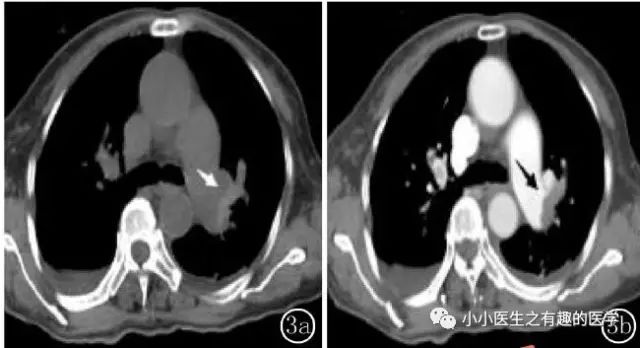

翠花上菜,学者上图。

发现嫌疑犯,立即逮捕。

增强CT对比,一目了然。

上面的患者,增强CT放大了。

下面是另外一个